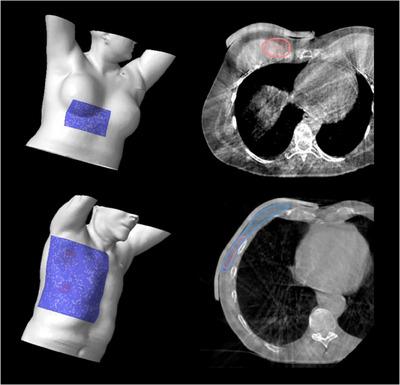

3D printed molds for bespoke bolus were created by exporting the DICOM structures of the bolus designed in the treatment planning system and manipulated to create a multipart mold for 3D printing. A silicone (Ecoflex 00-30) mixture is poured into the mold and cured to form the bolus. Molds for sheet bolus of five thicknesses were also created. A comprehensive FMEA was performed to guide workflow adjustments and QA steps.